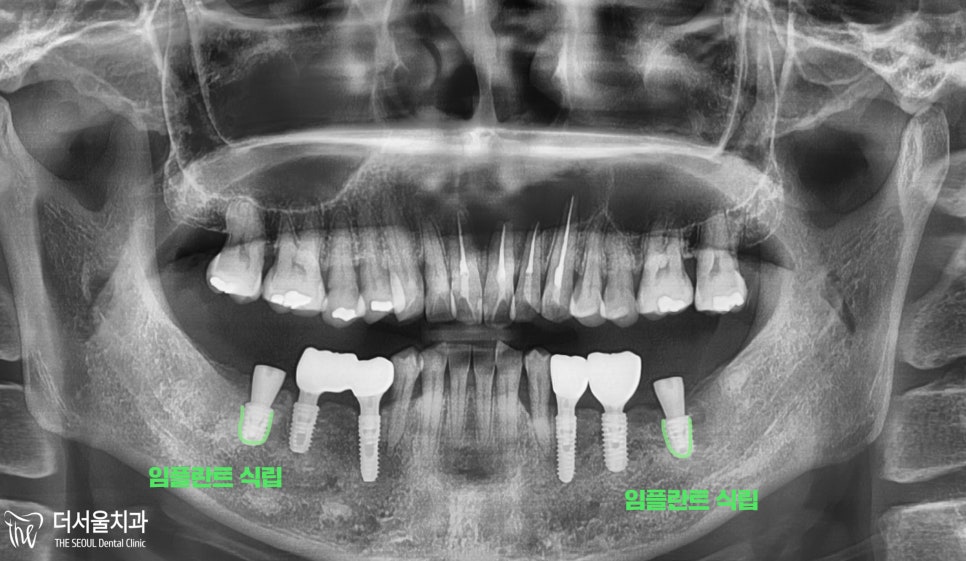

#37,47번 부위에

컴퓨터 분석 임플란트 를 진행한 모습입니다.

잇몸 절개 없이

계획한 부위에 픽스쳐를 심었으며

그 위에 힐링 어버트먼트를 체결하게 되었습니다.

그리고

적절한 골융합 기간을 통해서

임플란트 보철을 올려드릴 수 있었습니다.